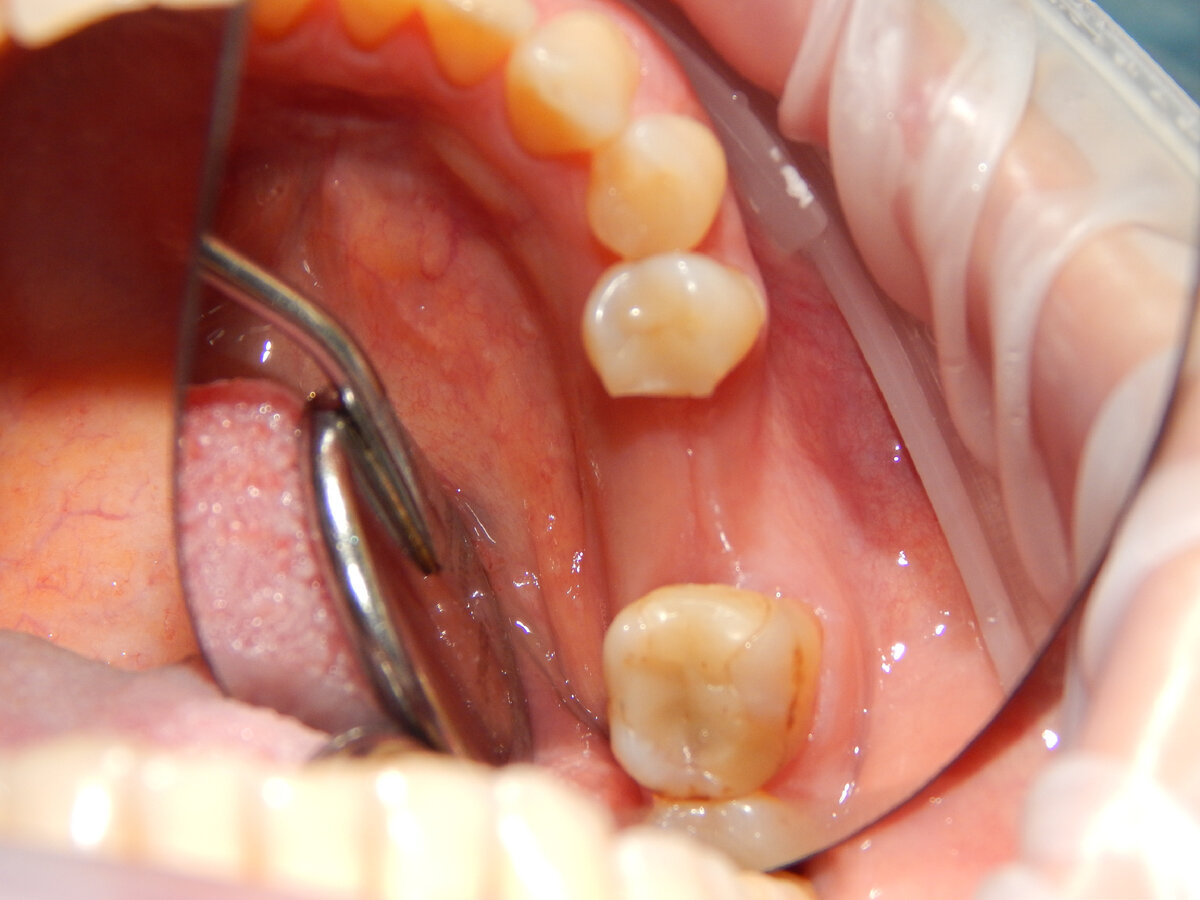

Ситуация до:

6 зуб слева снизу удален более 4 месяцев назад

Пациенту проведено сканирование, моделирование индивидуального шаблона в программе implant studio и его печать:

Железная штучка-втулка, по которой сверло опускается вниз в заданном направлении и никуда не смещается